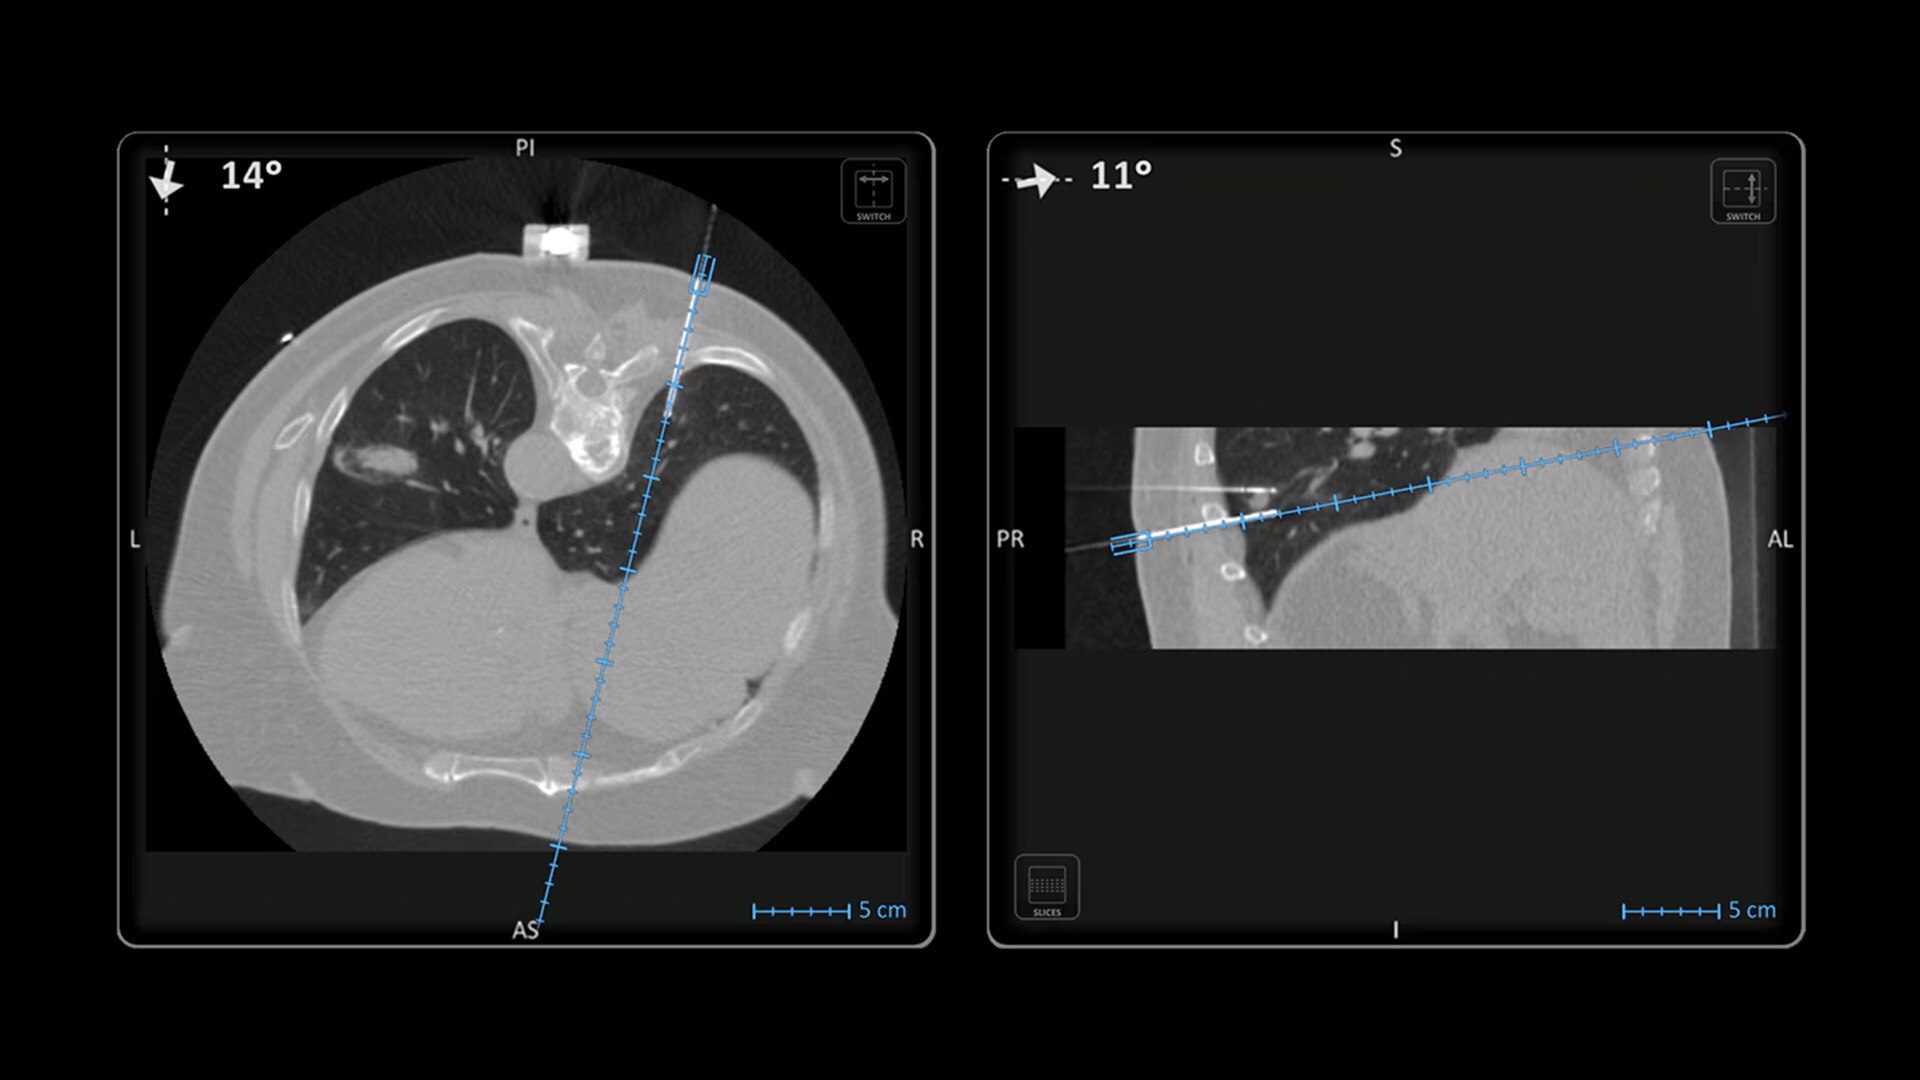

Imactis® CT-Navigation™

Planning and navigation solution for interventional percutaneous radiology that can increase procedure accuracy, reduce time, simplify workflow and reduce dose.¹

In interventional radiology, the success of the percutaneous procedure depends on correct needle positioning. The Imactis system helps the radiologist place one or more needles with great accuracy, in less time and with fewer control scans.

Accuracy

Imactis enables you to find the ideal path to the target.

With real-time image reconstruction, live interactive navigation and no limit in angulation, the optimal clinical choices are clear.

Live 3D needle tracking, precise reproduction of your planned trajectory and continuous needle depth measurement help ensure optimal needle placement.